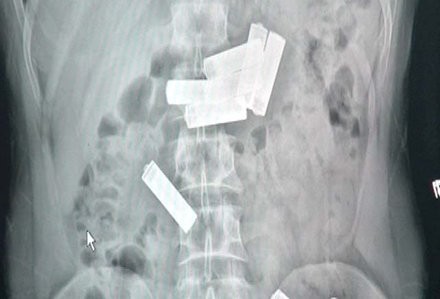

Acil serviste muayenesi yapıldıktan sonra çekilen röntgende D.K.'nin midesinde 8 kalem pil olduğu saptanınca Endoskopi Servisi'ne sevk edildi. Gastroenteroloji uzmanı doktor Ahmet Yağbasan başkanlığındaki ekip, yaptığı çalışma ile D.K.'nin midesindeki pillerin birisini çıkardı.

Uzmanlar, mahkumun midesindeki diğer 7 pilin müdahale yapılarak çıkarılmasının dokulara zarar vereceğini belirleyince takip altında doğal yollardan çıkarılması kararını verdi. Bunun üzerine servise yatırılan D.K., 2 gün sonra midesindeki pilleri doğal yollarla vücudundan çıkardı. Tedavisinin ardından taburcu edilen mahkum yeniden cezaevine gönderilirken, doktor Ahmet Yağbasan karşılaştığı manzaranın kendilerini şaşırttığını söyledi. İğne, boncuk ve bozuk para yutan hastalarla sıkça karşılaştıklarını ancak ilk kez midesinde 8 kalem pil olan bir vaka gördüklerini anlatan Ahmet Yağbasan, şöyle dedi:

"Vaka bize cezaevinden karın ağrısı şikayetiyle getirildi. Acil serviste çekilen röntgende midesinde kalem pillerin olduğunu belirledik. Bunun üzerine hastayı endoskopi ünitesine aldık. Midede 8 pil olduğunu gördük ve bunları özel aletlerle çıkarmayı denedik. Yaptığımız müdahale ile birini çıkardık ama diğerlerinin pozisyonu uygun olmadığı için çıkaramadık. Pillerin içindeki kimyasal maddelerden dolayı doku hasarına yol açabileceğine kanaat getirerek, hastanın diğer 7 pili takip altında doğal yollardan çıkarmasını kararlaştırdık. Serviste yatan hastamız 2 gün sonra pilleri doğal yollardan çıkarmış oldu."

Gaziantep'te, işlediği bir suç nedeniyle hükümlü olarak cezaevinde kalan ve rahatsızlanınca hastaneye kaldırılan mahkumun midesinden 8 kalem pil çıktı.